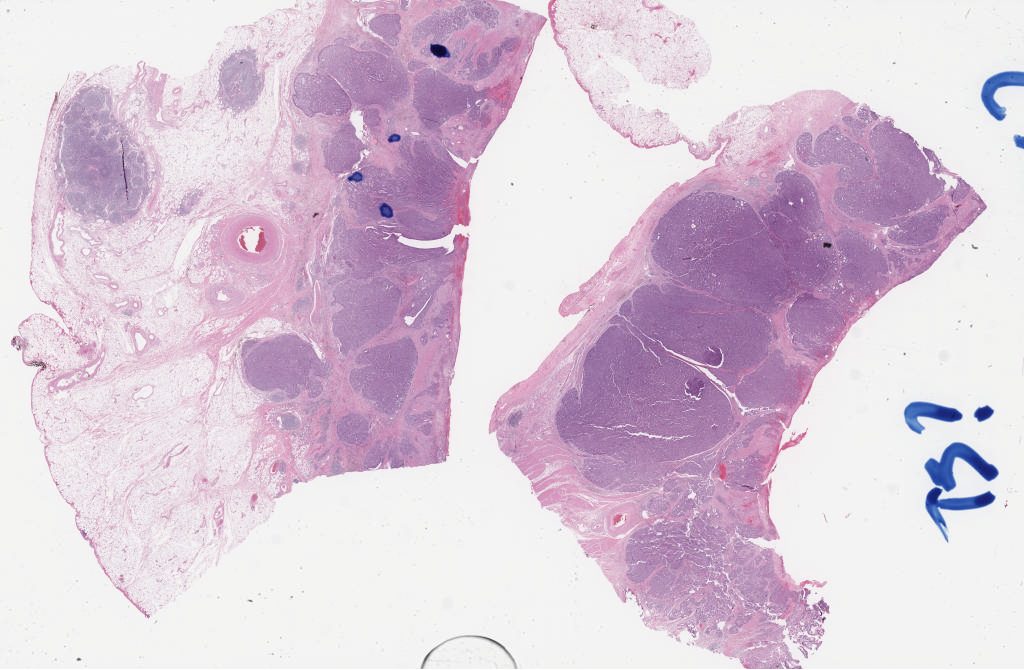

Case3 he 1i.svs

137448

x

89888

@

40X